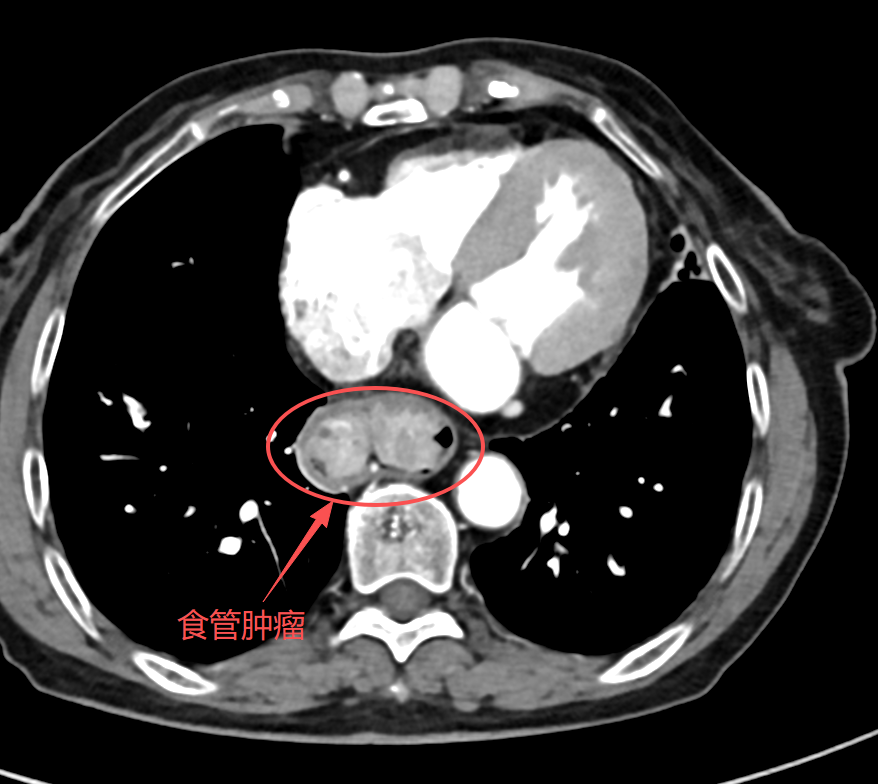

經(jīng)胃鏡及病理檢查,確診為早期食管癌——食管下段發(fā)現(xiàn)一處直徑約5cm的腫瘤,正是導(dǎo)致其進(jìn)食困難的“罪魁禍?zhǔn)住薄?/p>